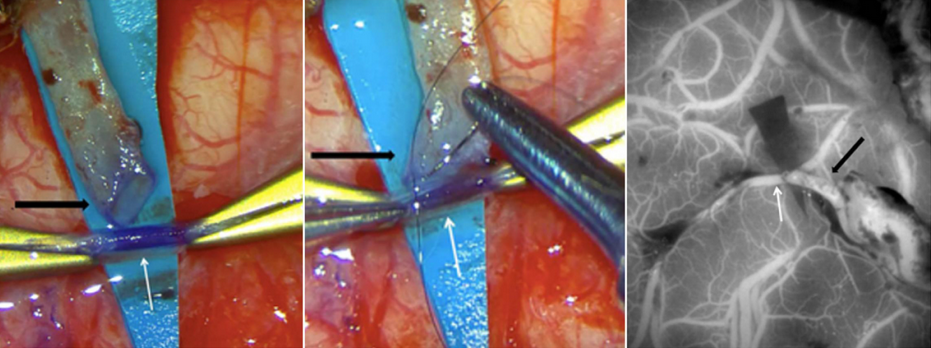

Figure 3: Images from a STA-MCA bypass surgery showing (a) the cut STA (black arrow), which has been dissected from the scalp and trimmed in preparation for use as a bypass donor, and prepared suture into the brain MCA vessel (white arrow), (b) the open end of the STA (black arrow) is being sutured onto the open MCA vessel (white arrow) and (c) intraoperative ICG dye angiogram showing blood flow through the skin vessel (black arrow) into the brain vessel (white arrow).